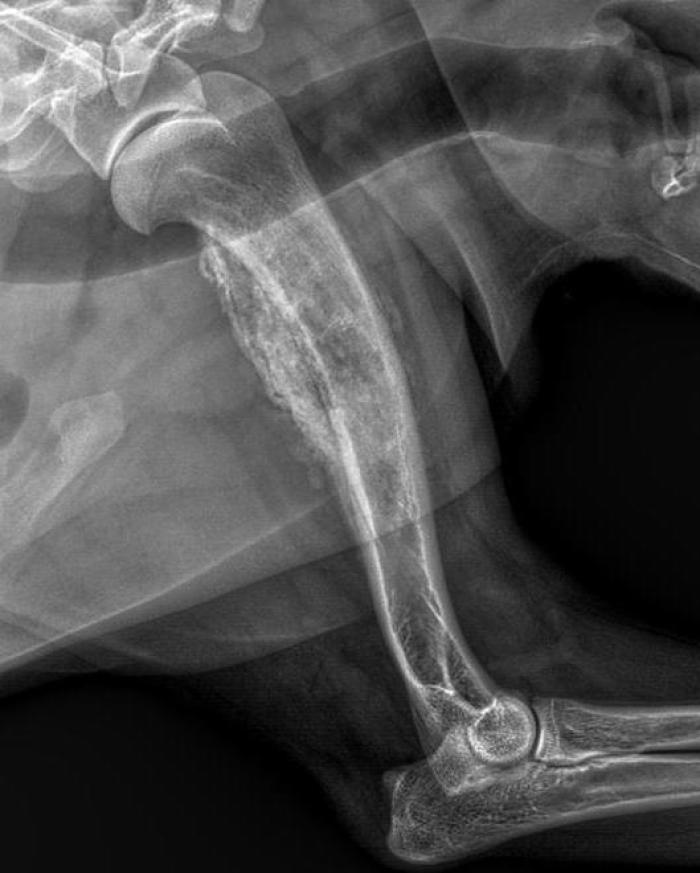

Se realizó un examen radiológico de las extremidades afectadas, en el cual se detectaron lesiones osteolíticas junto con periostitis (Figura 1).